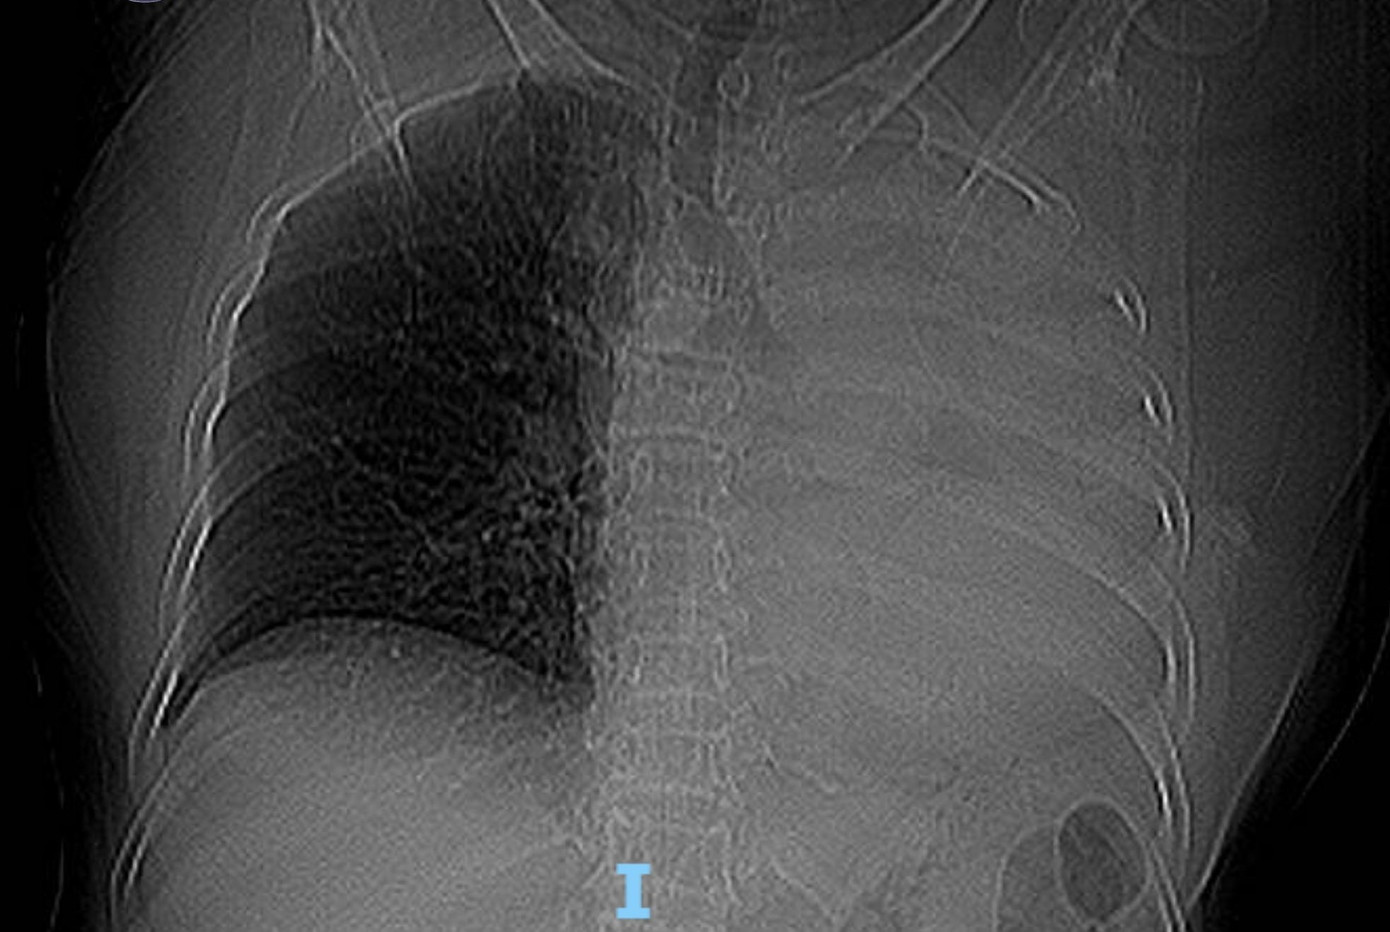

Bệnh nhân là bà T.B. (78 tuổi, trú Đà Nẵng). Sau khi chụp X-quang ngực, các bác sĩ phát hiện hình ảnh mờ đậm đều toàn bộ trường phổi trái. Kết quả CT cho thấy cụ bà bị xẹp toàn bộ phổi trái do khối tổn thương nằm trong lòng phế quản gốc trái, nghi ngờ u phế quản hoặc dị vật đường thở.

Phim X-quang ngực cho thấy mờ toàn bộ phổi trái.